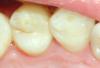

АнтонТЛТ Опубликовано 13 апреля, 2013 Поделиться Опубликовано 13 апреля, 2013 26 чуть доработать и сделать коронку. Я бы так сделал. Ссылка на комментарий

METT Опубликовано 13 апреля, 2013 Автор Поделиться Опубликовано 13 апреля, 2013 26 чуть доработать и сделать коронку. Я бы так сделал.Мне в клинике тоже сказал наш реставратор-ортопед))но у меня так вышло-решил зачем стачивать более-менее сохранившийся бугор) Ссылка на комментарий

АнтонТЛТ Опубликовано 13 апреля, 2013 Поделиться Опубликовано 13 апреля, 2013 Чтобы потом не откололся Ссылка на комментарий

METT Опубликовано 13 апреля, 2013 Автор Поделиться Опубликовано 13 апреля, 2013 Чтобы потом не откололсяБуду надеяться что не сколится.ИМХО.) Ссылка на комментарий